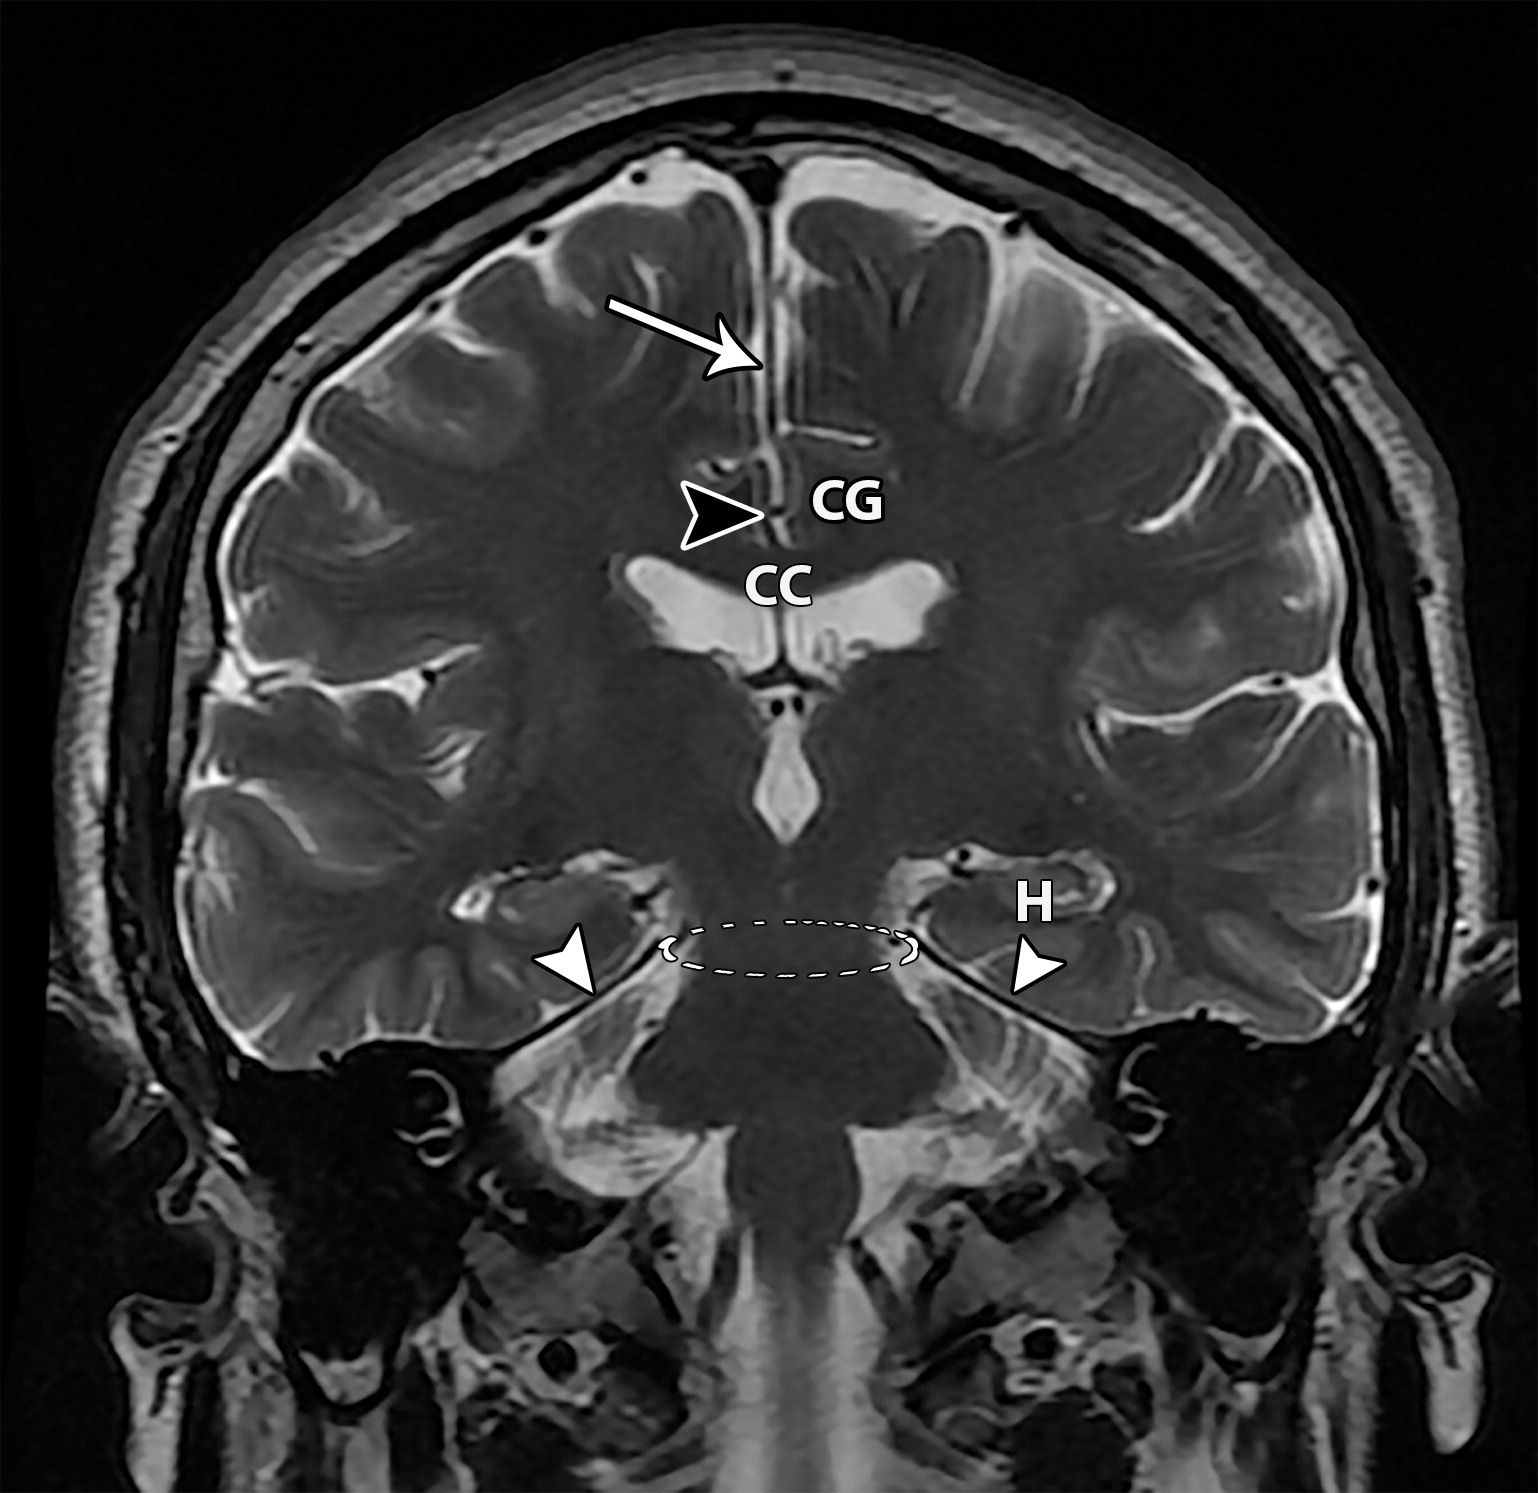

8661e4013eed444f2a047a191a475a2a.jpeg

位于大脑半球裂之间的大脑镰(白色长箭头),小脑幕(白色短箭头),小脑幕切迹(点状卵圆形圈出的结构),胼胝体(CC),扣带回(CG),海马(H),胼胝体周围沟及胼周动脉(黑色短箭头)。